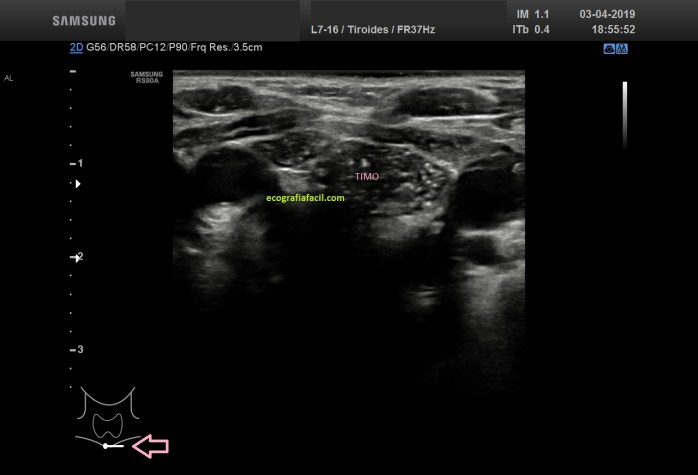

En las figuras 4 y 5 verás el aspecto del Timo, extratiroideo, fíjate en el pictograma. En este caso vemos que tiene una semiología en forma de cielo estrellado, hipoecogénico con gran cantidad de puntos hiperecogénicos.

In figures 4 and 5 you will see the aspect of the thymus, extrathyroid, look at the pictogram.

In this case we see that it has a semiology in the form of starry sky, hypoechogenic with a lot of hyperechogenic points.